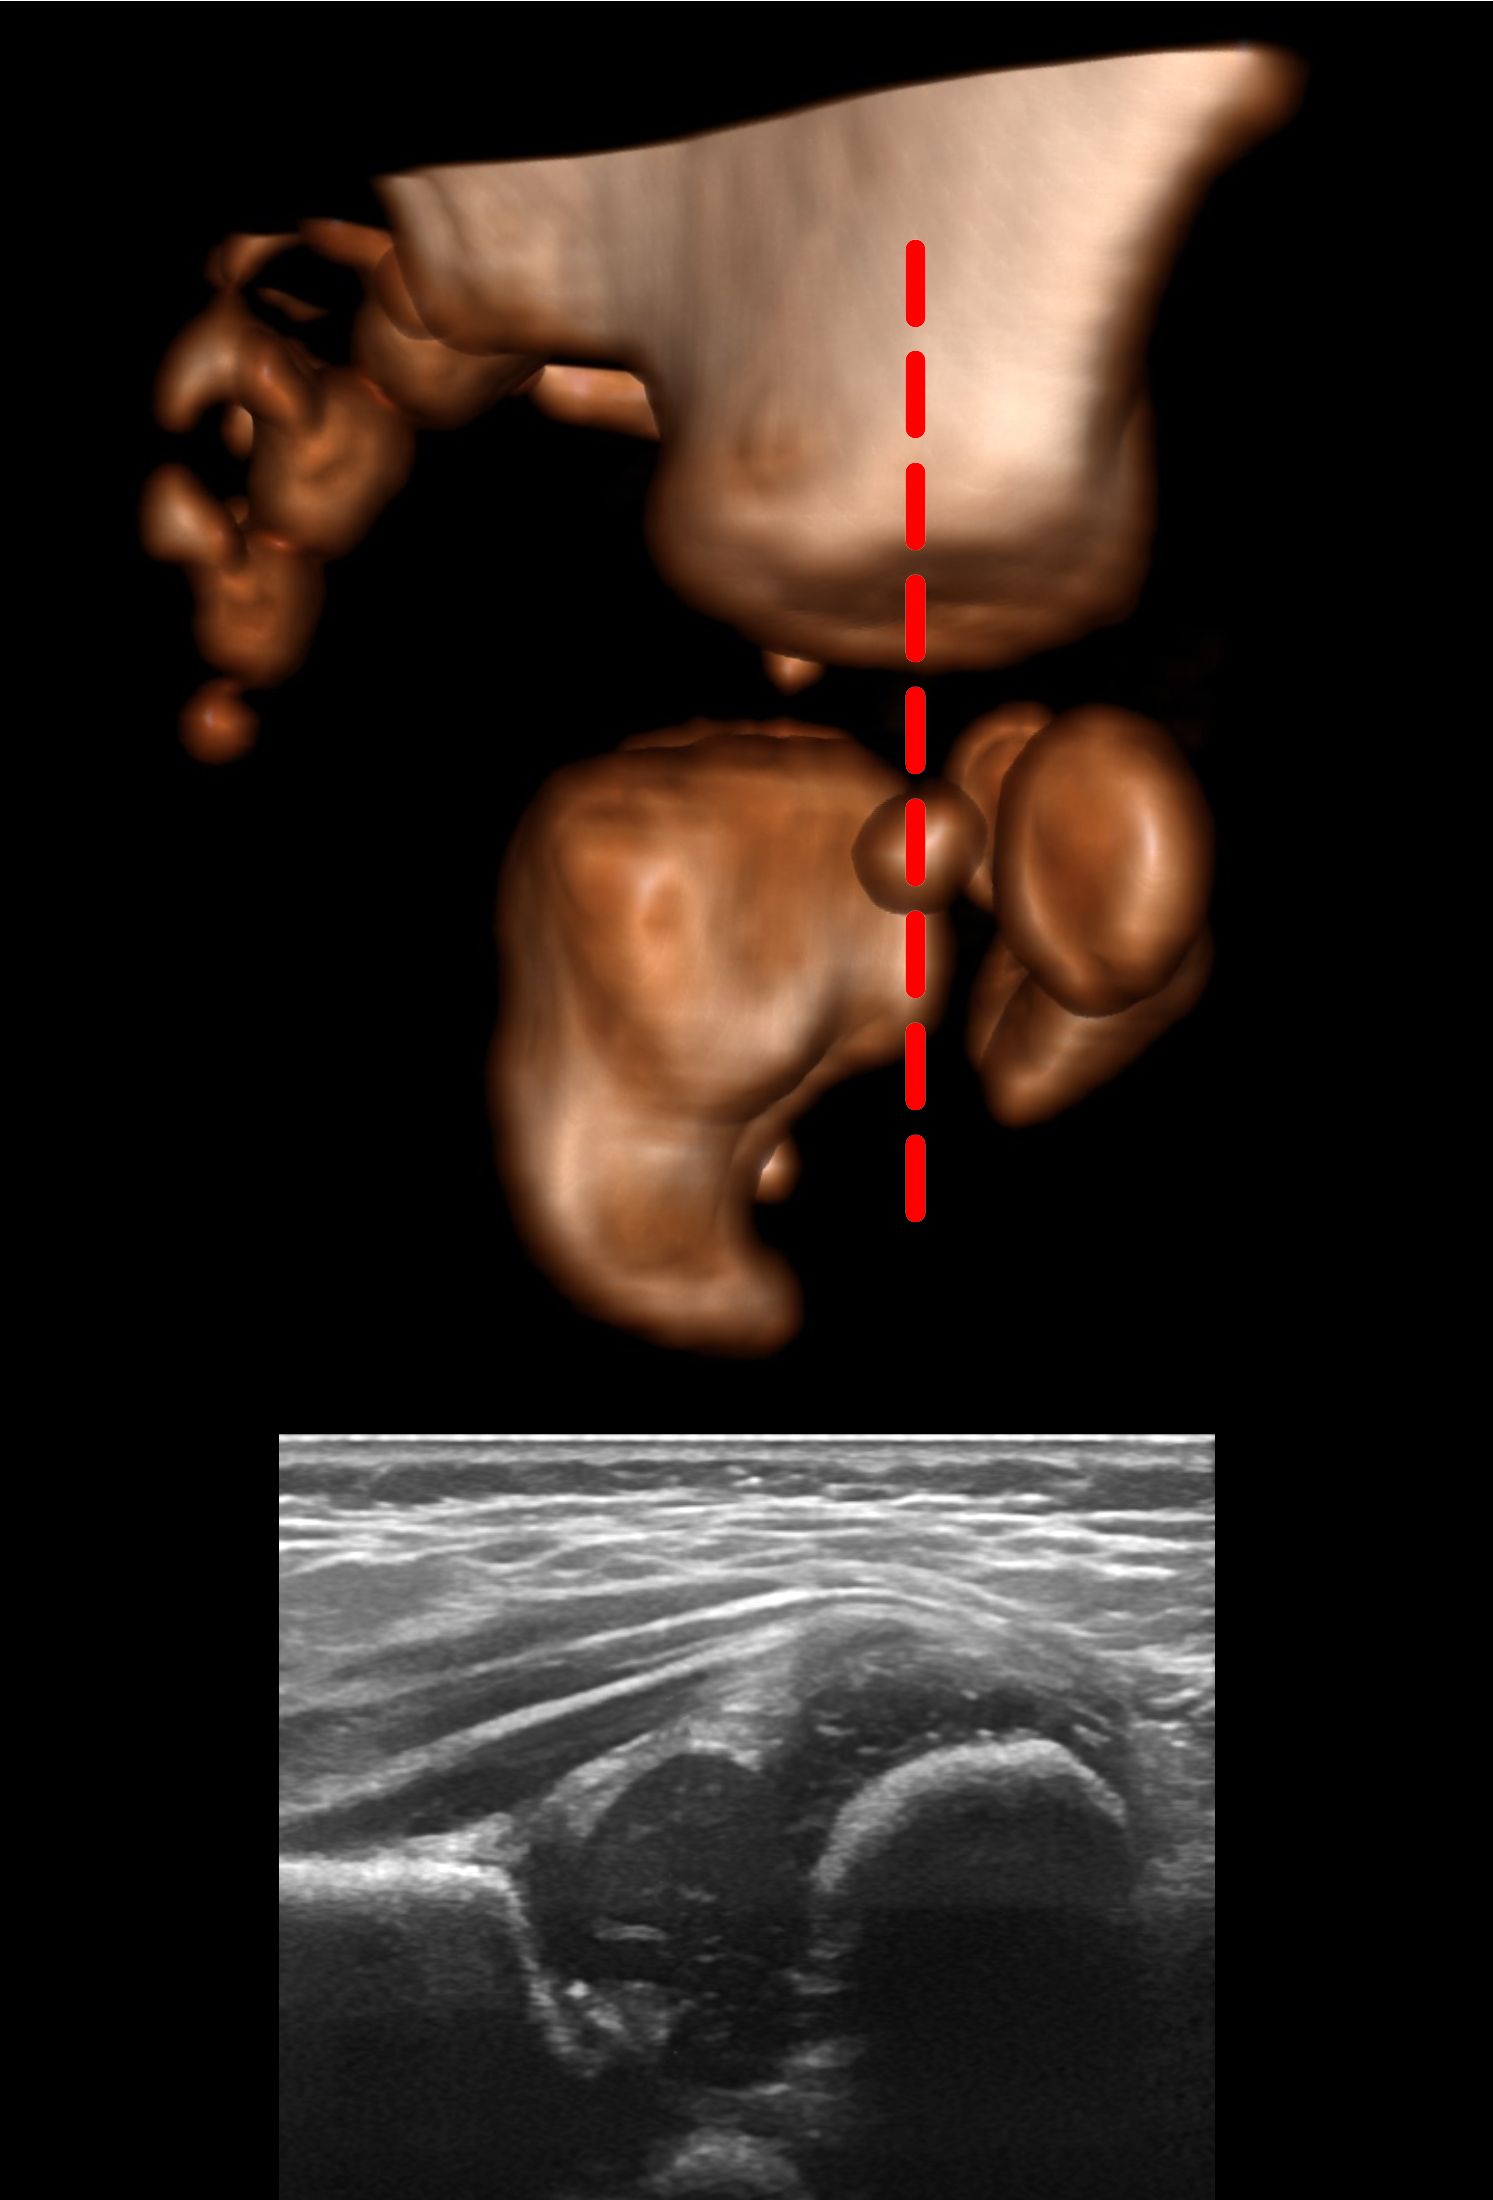

Using the Graf method the hips should be slightly flexed [1, 2]. The patient should be on their side and the probe is placed, vertically orientated, on the lateral aspect of the hip.

After identifying the osteochondral junction, the femoral head, synovial fold, joint capsule, acetabular labrum, acetabular cartilage, bony roof of the acetabulum and turning point (see earlier) should be identified. The lower limb of the ilium and the triradiate cartilage indicate the acetabular center. The ilium should then be made straight on the screen. Since, at this point, the ilium raises anteriorly and superiorly and falls posteriorly and inferiorly, to get a straight image of the ilium, you need to align the probe between the rise and the fall.

If you are scanning the right hip, rotating the probe clockwise will result in the part of the image formed by the top of the probe to raise in a curve:

And if you rotate anticlockwise, it will cause it to fall as a curve:

So to make a straight line you either chase it down by rotating anticlockwise or raise it up by rotating clockwise whilst maintaining the centre of rotation such that the structures of interest remain on screen. The opposite rotation is needed when scanning the left hip.